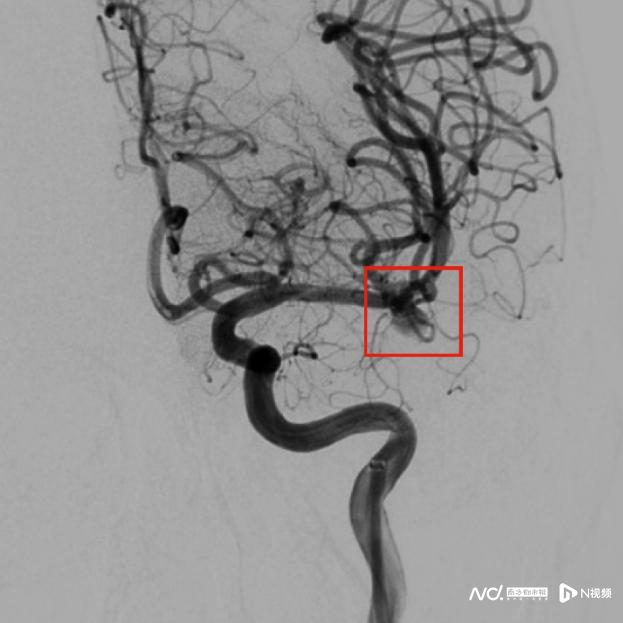

植入安装后动脉瘤腔内血流瘀滞较着缩小

“瘤内扰流安装就像一把放在动脉瘤里的‘保护神’。”段传志主任阐发,动脉瘤会离散是因为血流一直往里冲,咱们研发的安装就放在动脉瘤内,给与双层网结构,外层把冲进来的血液径直挡住,让血流改谈,走向双方平方的血管;内层让动脉瘤里面残留的血液停驻并凝固,从而透顶幸免离散风险。

瘤内扰流安装通过物理花样,即刻封堵动脉瘤颈,开释经过中能最大遏抑镌汰对开释角度的影响,无需支架援手,无需填塞弹簧圈,一根导管一步到位,把复杂的分叉部动脉瘤调节变得简便快速透顶。